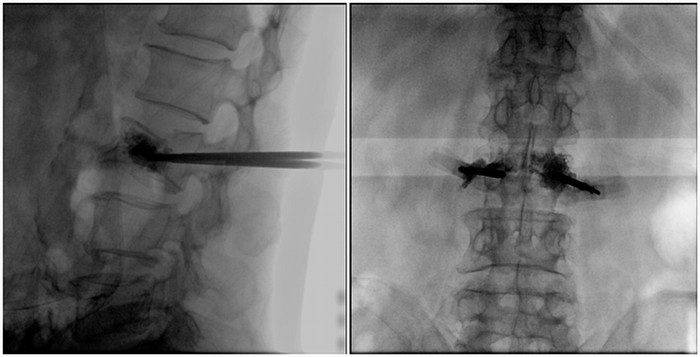

普愛醫(yī)療大平板一體式移動C臂采用30cm×30cm的平板探測器,能在手術(shù)過程中,為醫(yī)生提供更廣闊的視野范圍,帶給醫(yī)生更全面的影像信息。在進行脊柱類手術(shù)時,一次曝光即可呈現(xiàn)全節(jié)段腰椎,避免因為呈像不全而導致重復(fù)曝光,不僅提高了手術(shù)效率,而且避免醫(yī)生吸收過量的輻射。